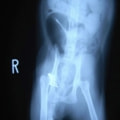

症例3:キルシュナーワイヤーのピンニングによる整復

ペルシャ猫 11ヶ月齢 雄

他院にて左大腿骨遠位の成長板骨折(salter-harrisⅠ型)が認められており、治療相談を目的として来院。当院にて、キルシュナーワイヤーを用いたピンニングにより骨折部位の整復を行いました。術後の経過は良好で、現在も経過観察中です。

術前レントゲン

術後レントゲン

Arthrex社のターゲティングデバイスを用いてピンニングの位置を調整することで、確実な固定を行っています。当院ではこの手術器具以外にも、人の手術にも使用される様々な器具を導入し、手術精度を高め、また医療メーカーと新しい器具の開発、試作にも取り組んでおります。